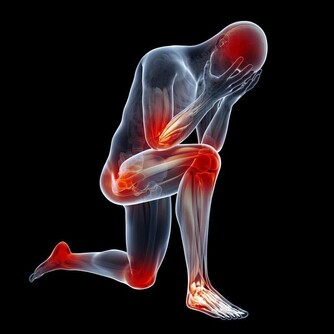

頸椎病現在的基本概念,是以頸椎椎間盤退變為主要病變基礎,包括頸周圍肌肉、關節繼發性改變和相鄰椎體退變增生直到壓迫神經血管等,並誘發與之相關臨床病症和體徵。

長期頸部前伸、頭部前屈,頸後部肌肉、韌帶就會處於被牽張的狀態,超過30分鐘時就會有疲勞感。超過2小時,就會造成肌肉、韌帶拉傷。長期下來,頸椎生理曲度變小、消失或反張,對椎間盤的支撐和保護作用下降,這時就容易出現頸椎病啦。